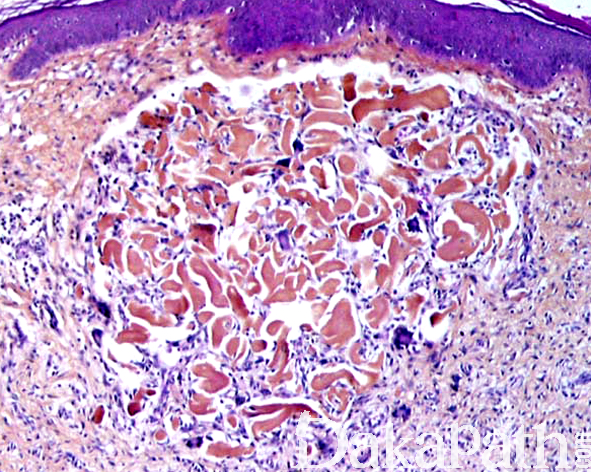

镜下显示在典型的皮肤纤维组织细胞瘤/真皮纤维瘤组织背景中、在真皮的浅层可见界限清楚的由粗大的胶原纤维聚集形成的结节;

结节周围可见灶性出血、含铁血黄素沉着及数量不等的多核巨细胞反应;

瘢痕疙瘩样结节的表皮显示萎缩性改变。